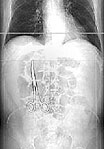

Most lost objects were sponges, but also included were metal clamps and electrodes. In two cases, 11-inch retractors metal strips were forgotten inside patients. In another operation, four sponges were left inside someone.

The lost objects were usually lodged around the abdomen or hips but sometimes in the chest. They often caused tears, obstructions or infections. Most patients needed additional surgery to remove the object. In other cases, patients were not even aware of the object, and it turned up in later surgery for other problems.